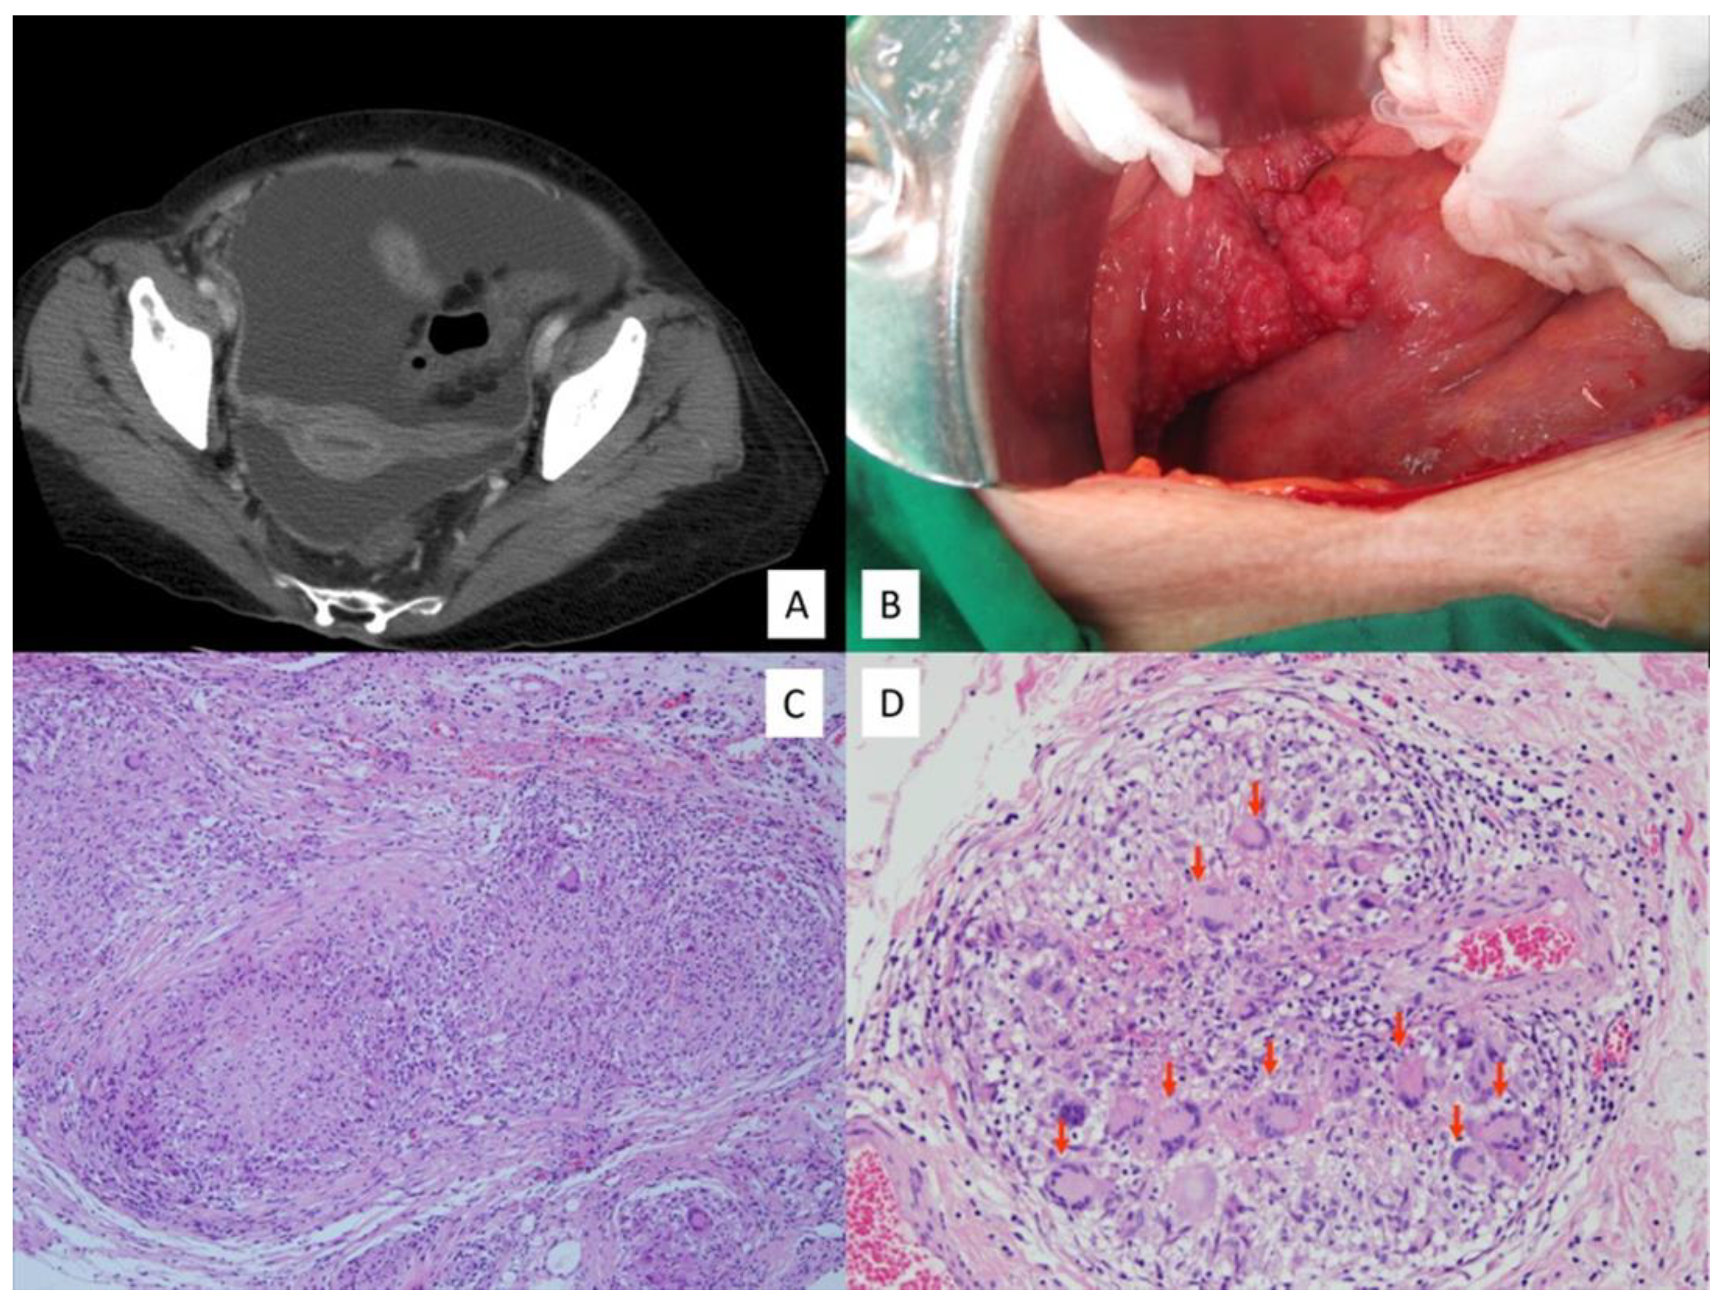

3.2. Radiologic Characteristics

3.3. Intraoperative Findings